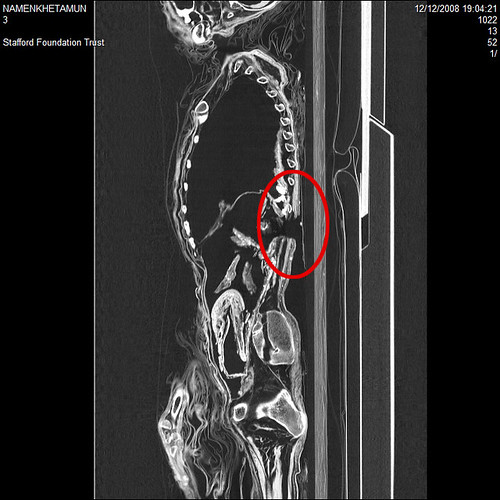

One of the mummies, from the Namenkhetamun of the 26th Dynasty (664-525BC), was described as ‘the daughter of Amunkhau’ on the coffin lid. But the scan has revealed the mummy is male. Researchers also discovered another mystery – an unexplained hole in the mummy’s back, about the size of a fist.